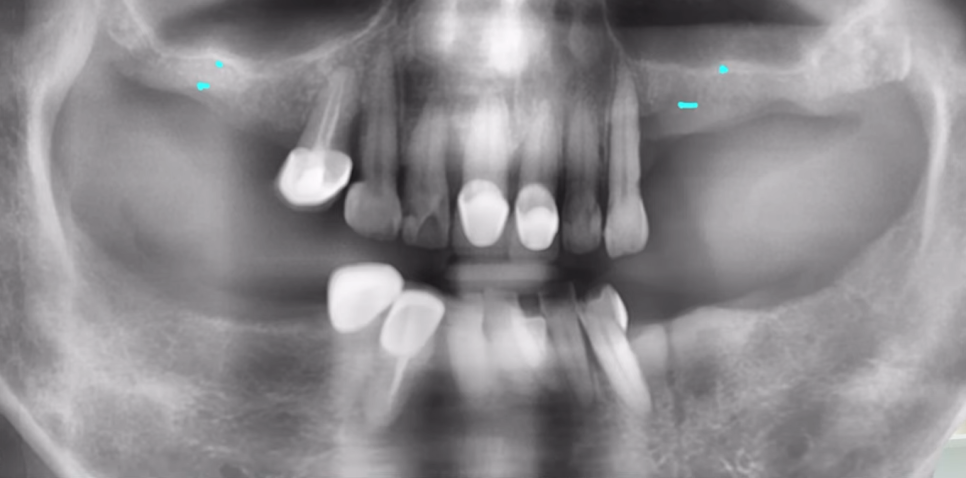

하나 사례를 들고 와봤는데요.

48세 여성 환자분이셨는데, '오른쪽 아래 치아가 아파요'라며 찾아주신 분입니다.

살펴보니 우측 제1대구치가 금이 가서 더 이상 유지가 어려운 상태였지요.

결국, 환자분의 동의를 받고 발치하였는데요.

감염도 거의 없고, 엑스레이 상 치조골도 잘 보존되어 있었기에 그날 바로 심어드렸습니다.

임플란트도 좋은 각도로 심고, 힐링 어버트먼트까지 잘 심어드렸습니다.

이렇게 발치 후 즉시 임플란트가 가능하려면 발치한 자리에 남은 뼈가 온전해야 합니다.

이를 뽑고 나면, 그 자리에 잇몸뼈가 남는데

이 뼈가 무너지지 않고 건강하게 남아 있어야 임플란트를 단단히 고정할 수 있거든요.